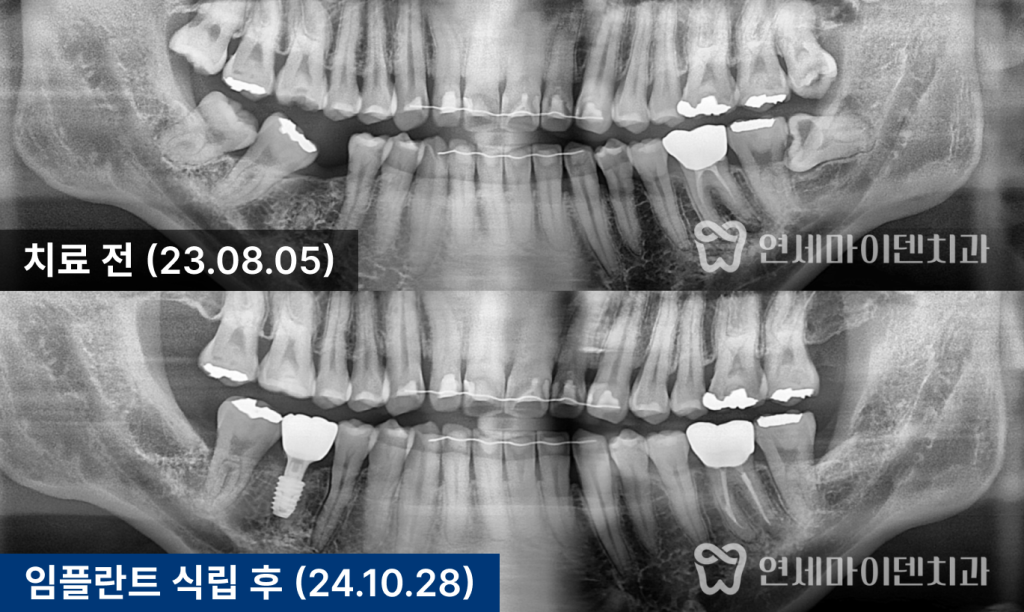

앞 치아는 자연치로 살렸습니다.발치 후 상태와 문제점

환자분은 오랫동안 통증을 참고 지내다

결국 어금니 하나를 발치한 상태로 내원하셨습니다.

X-ray를 확인해보면,

반대편 어금니는 뼈 상태가 비교적 건강한 반면문제 부위는 치조골 높이가

절반 가까이 무너진 상태였습니다이 때문에 이전 병원에서는

“앞 치아도 곧 못 쓴다”며

두 개 모두 임플란트를 권유받았던 상황이었습니다.

하지만, 앞쪽 어금니의 경우

뿌리 앞쪽 뼈는 비교적 단단하게 남아 있었고

염증 범위도 제한적이어서

충분히 보존 가능성이 있는 상태였습니다.즉,

무조건 두 개를 다 뽑아야 할 상황은 아니었습니다.치료 방향: “하나는 살리고, 하나는 심자”

그 결과,

수술 후 X-ray에서 뼈 높이가 뚜렷하게 상승했고

앞쪽 어금니의 흔들림도 눈에 띄게 줄어들었습니다.3년 경과 후 결과

치료 후 3년이 지난 현재까지도

임플란트, 보존한 자연치

모두 안정적으로 유지되고 있습니다.초기에는 뼈가 절반밖에 남지 않았던 부위가

뼈이식 후 건강한 높이로 회복되었고,

그 결과 임플란트 하나가

옆 자연치의 수명까지 함께 늘려준 셈이 되었습니다.